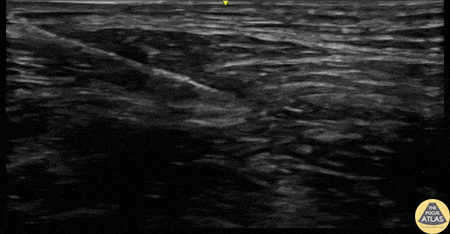

A 60s F presented with hip pain after a recent fall. Radiographs showed a subacute femoral neck fracture. To aid with pain control, a fascia iliaca compartment nerve block was performed. The needle is seen here popping through the fascia iliaca, just superficial to the iliacus muscle, before injecting anesthetic just below the fascia iliaca. This injection was somewhat intramuscular. The expansion of the anesthetic pocket with injection and collapse when injection is paused helps confirm that anesthetic is spreading along the fascial plane rather than pooling in a contained area within muscle. Joseph Ponce, PGY-3 Denver Health Residency in Emergency Medicine